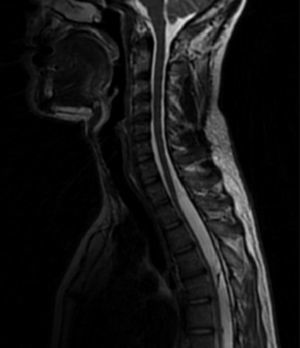

Mediante RM craneal con y sin contraste y angio-RM venosa se descartaron lesiones ocupantes de espacio, alteraciones de la charnela occipitocervical, trombosis de senos venosos y captaciones patológicas de contraste. Se realizó punción lumbar, que muestra LCR de aspecto claro con presión de apertura de 15cm de agua, acelular, glucorraquia normal y proteínas elevadas (81mg/dl). Se completó el estudio con RM medular, objetivándose colecciones líquidas sugestivas de quistes aracnoideos, intradural desde el nivel T1-T2 hasta T9 (fig. 1) y extradural (fig. 2) desde T11 hasta L5, que ocasionan desplazamiento anterior de la médula y de las raíces de la cola de caballo; no se objetivó realce tras la administración de contraste. El paciente desestimó tratamiento quirúrgico.